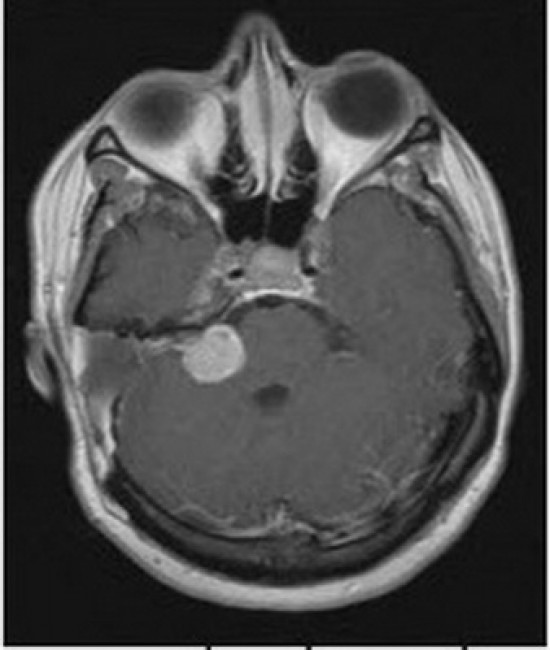

Trong số các nguyên nhân điếc đột ngột, khoảng 0,8 - 4% người bệnh có u ống tai trong hoặc u góc cầu - tiểu não (xem ảnh), ngay cả khi người bệnh đã hồi phục thính lực hoàn toàn cũng không thể hoàn toàn loại trừ các nguyên nhân này. Do đó, chụp cộng hưởng từ (MRI) có tiêm gadolinium là xét nghiệm phù hợp nhất để loại trừ các bệnh lý sau ốc tai. Nếu không thể chụp cộng hưởng từ, người bệnh nên được đo điện thính giác thân não hoặc đo lại thính lực đồ trong quá trình điều trị, các bất thường kéo dài trên 2 xét nghiệm này có thể gợi ý cho các bệnh lý sau ốc tai.

Khối u thần kinh tiền đình ở góc cầu - tiểu não gây điếc đột ngột.